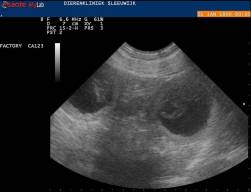

Echofoto 04